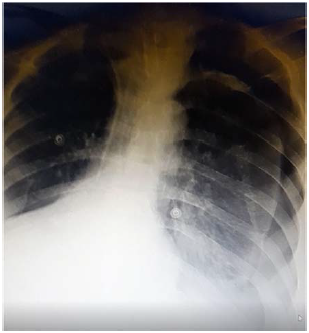

Um paciente de 50 anos de idade encontra-se, internado na UTI por conta de choque séptico de foco pulmonar, em ventilação mecânica na modalidade pressão e no modo assisto-controlado. Pela manhã foi submetido a acesso venoso central em veia axilar guiado por ultrassonografia. Ao exame físico, notou-se que o paciente está com hipotensão e taquicardia. A primeira hipótese diagnóstica é pneumotórax e é realizada radiografia com imagem apresentada.

De acordo com a imagem, a